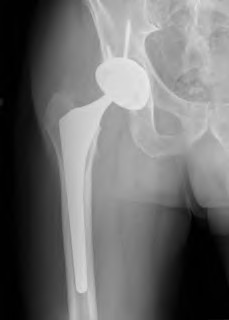

A 67-year-old man who underwent total hip arthroplasty (THA) 4 years ago fell on to his right hip. His pre-injury right hip film is seen in Figure A while films of his current injury are seen in Figures B and C. Prior to the fall he had no thigh or hip pain. His ESR and CRP are within normal limits. During intraoperative assessment, the acetabular and femoral stems are found to be well fixed. What is the next best course of action?

This patient has a periprosthetic hip fracture at the level of the stem with a stable prosthesis, indicated open reduction and internal fixation as the treatment of choice.

The Vancouver Classification can be helpful in clinical decision-making regarding fixation versus revision of periprosthetic hip fractures of the proximal femur. A stable implant, by nature, does not need to be revised in the setting of adequate bone stock for fixation, but the ultimate test of stability should be in the operating room. Many fixation strategies are appropriate, but many implants include locking plate fixation for concerns of stress-shielded bone around the implant as well as use of unicortical fixation at the level of the stem.

Pike et al review the current trends in treating B1 fractures including locking plates with strut allografts, minimally invasive plate osteosynthesis (MIPO) and locking plates spanning femoral THA and TKA stems in selected patients. The authors conclude that no studies currently provide evidence establishing one

Illustration A shows a possible fixation construct for this patient's fracture. The Vancouver Classification is seen in Illustration B and Illustration C represents an algorithm for treatment options.